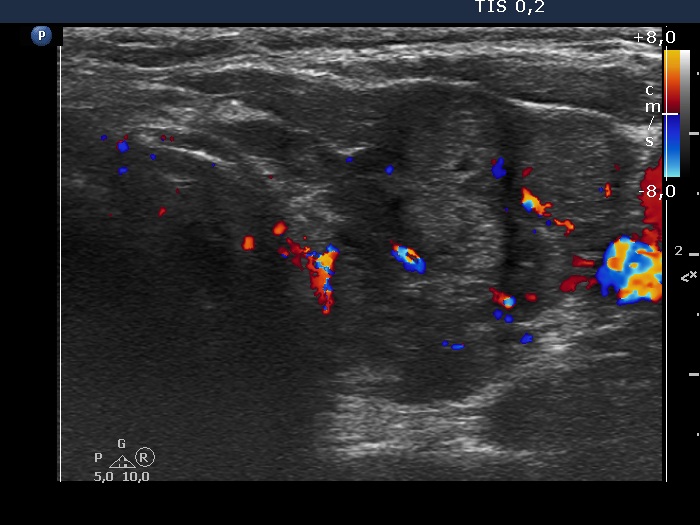

Discrete lesion or nodule in Hashimoto's thyroiditis - case 28 (1124) (ultrasonographic picture 11)

Left lobe, transverse scan, color Doppler mode. The vascularization is a not specific.